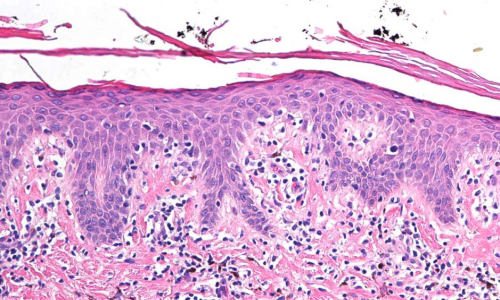

体型?职业?竟然也是引发皮肤起癣的原因!

生活节奏飞速前行,伴随而来的各种疾病也呈现上升趋势。世界卫生组织(WHO)宣布,皮肤病将是21世纪人类历史上发病率最高、致残率最高、传染性最强的一种疾病,而医疗数据

为皮肤起癣的原因做减法,让真菌迅速远离

身上起癣是什么原因?当真菌侵袭头部或身体的皮肤外层时就会出现真菌感染。比如个人生活习惯,卫生,饮食,以及环境恶劣,夏季温暖,雨季潮湿等都是引起癣病的源头。真菌归